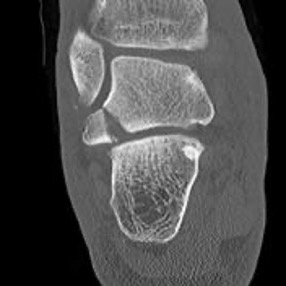

CT

McCrory-Bladin Classification

| Type I |

Type 2A |

Type 2B | Type 3 |

|---|---|---|---|

|

Chip fracture Doesn't involve articular surface |

Larger fracture Involves articular surface talofibular & subtalar join Undisplaced |

Larger fracture Involves articular surface talofibular & subtalar joint Displaced |

Comminuted fracture Involves articular surface talofibular & subtalar |